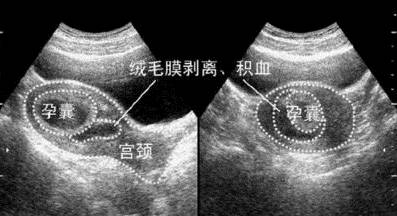

胚胎着床后会在表面形成绒毛膜,是构成胎盘的胎儿部分。当绒毛膜和子宫壁分离时会引起出血,出血量不固定,颜色偏暗,亦可无症状,仅在B超检查时发现孕囊周围的低回声出血区。如果无阴道流血或少量阴道流血不伴其他异常情况,多自然停止出血,不影响胎儿预后;如阴道出血量大、持续时间长、伴腹痛,B超提示出血面积增加可能导致宫内感染或不可避免的流产。

(图:B超下绒毛膜血肿)